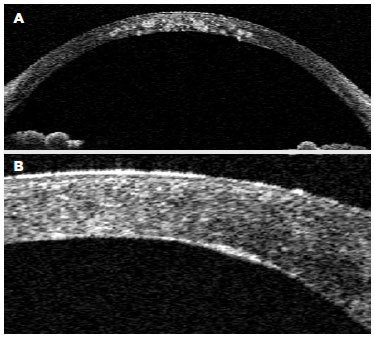

We performed Visante optical coherence tomography (OCT)® (Carl Zeiss Meditec, Dublin, CA, USA) which showed hyperreflective granules from the Bowman's layer to the deep stromal lamellae, indenting the DM in some areas (Figure 2 A).

Figure 2. A) Visante OCT® image showing hyperreflective granules with clear intervening stroma from the Bowman's layer to the deep stromal lamellae, indenting the DM in some areas; B) One-month post-operative Visante® OCT image showing hyperreflective opacities between the donor cornea and the recipient's DM, which demonstrates persistence of dystrophy deposits inside the predescemetic layer.

Post-operative anterior biomicroscopy with scleral scattering illumination showed persistence of whitish granules in the recipient's cornea (Figure 4 A), which were identified as being anterior to the DM and posterior to the donor cornea using a slit lamp (Figure 4 B). Visante® OCT was performed one month post operatively and showed hyperreflective opacities between the donor cornea and the recipient's DM, demonstrating persistence of dystrophy deposits inside the predescemetic layer (Figure 2 B). Her BCVA improved to 20/60 in the first month even with opacities near the visual axis.

In the present study, there was no dystrophy recurrence. Instead, we found persistence of GCD1 deposits in the predescemetic layer after Type-1 Big Bubble DALK. GCD1 diagnosis was confirmed with unequivocal pathological analysis with Masson trichrome staining and topography of persistent deposits was indicated by the surgical technique (which kept the predescemetic layer intact using a Big-Bubble Type-1 technique) as well as by Visante OCT® imaging showing the persistence of deposits just anterior to the DM.